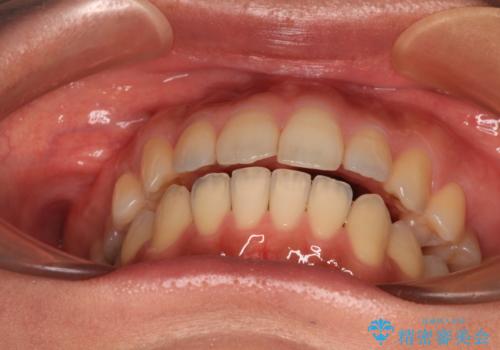

舌のトレーニングをしっかりと行ってくださり、前歯部のオープンバイトは大幅に改善されました。

もう少しでよりタイトに前歯が接触できそうでしたが、患者様がもう十分とのことで治療を終了しました。